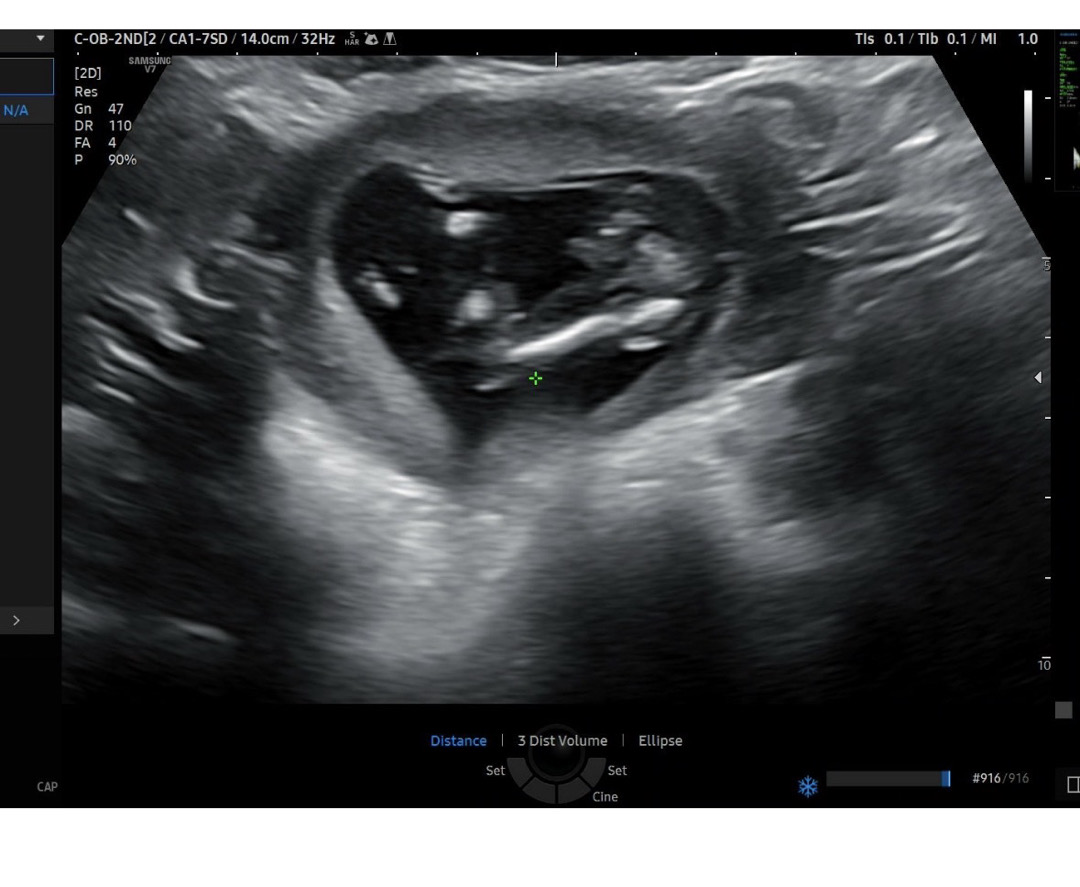

14주차 다리사이로 보이는게 그게맞을까요..?

14주라서 아직은 잘모른다고 하시긴하는데 너무 고추같아 가지구요 ㅎㅎㅎㅎ 여러분이 보기엔 어떠신가요?